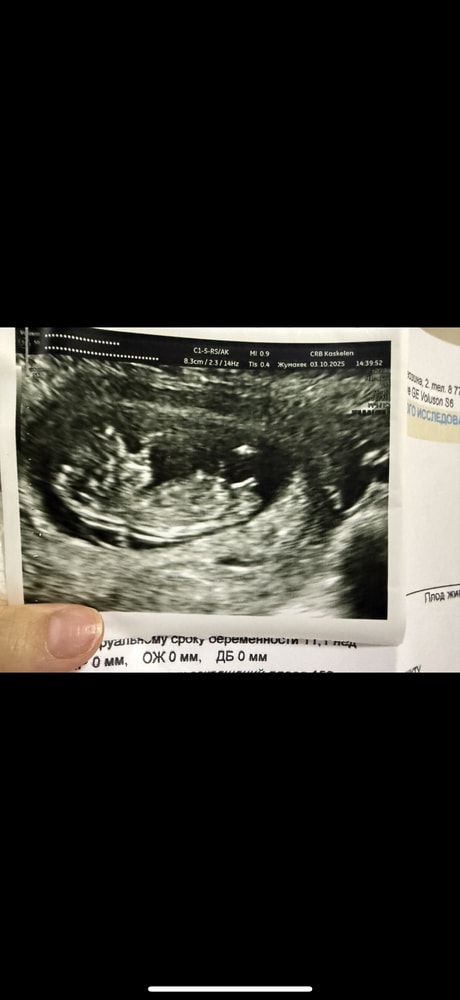

Kamo Isak в Клуб беременных 2 месяца Узи посмотрите одинаковые?) Пол малыша Девочки посмотрите эти фотки похожие ?)первый мойвторой из интернета,где выявили мальчика ..)) Посмотрите еще 20 записей на эту тему Отменить Ответить Погадаем ))) Девочка же? Чаты Беременных Выберите чат: Январята-2026 Февралята-2026 Мартята-2026 Апрелята-2026 Майчата-2026 Июнята-2026 Июлята-2026 Августята-2026